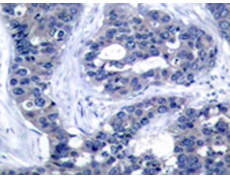

IHC positive control: |

Human breast carcinoma |